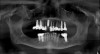

Fig 2. Preoperative radiograph revealing the failing implant at No. 13 that would be explanted; then the site would be curetted and a new, wider-diameter implant placed.

Figure 2